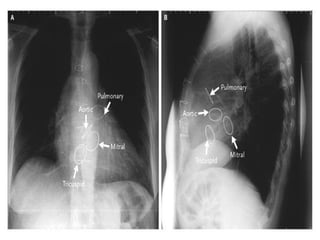

Cardiac valves

Atria are reservoirs of blood but the

ventricles are pumps of the blood. The

blood has one sided blood flow from veins

into atria, from atria into ventricles, from

ventricles into arteries. This property is

due to activity of valves.

Atrio-ventricular valves – tricuspid in right

and mitral valve in left heart prevent back

flow from ventricles into atria.

Semilunar valves between the left ventricle

and aorta, between right ventricle and

pulmonary artery prevent back blood flow.